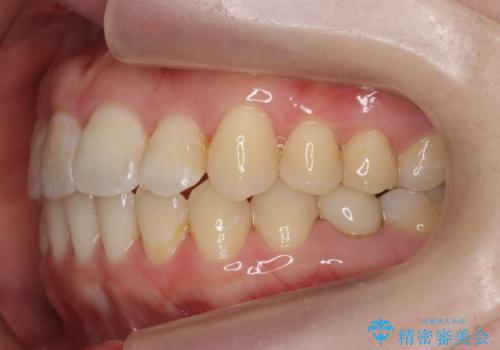

犬歯のねじれ 上の歯が引っ込んでいる

- 前歯の並びを気にして来院。

インビザラインで、上の前歯をやすり掛けして並べました。